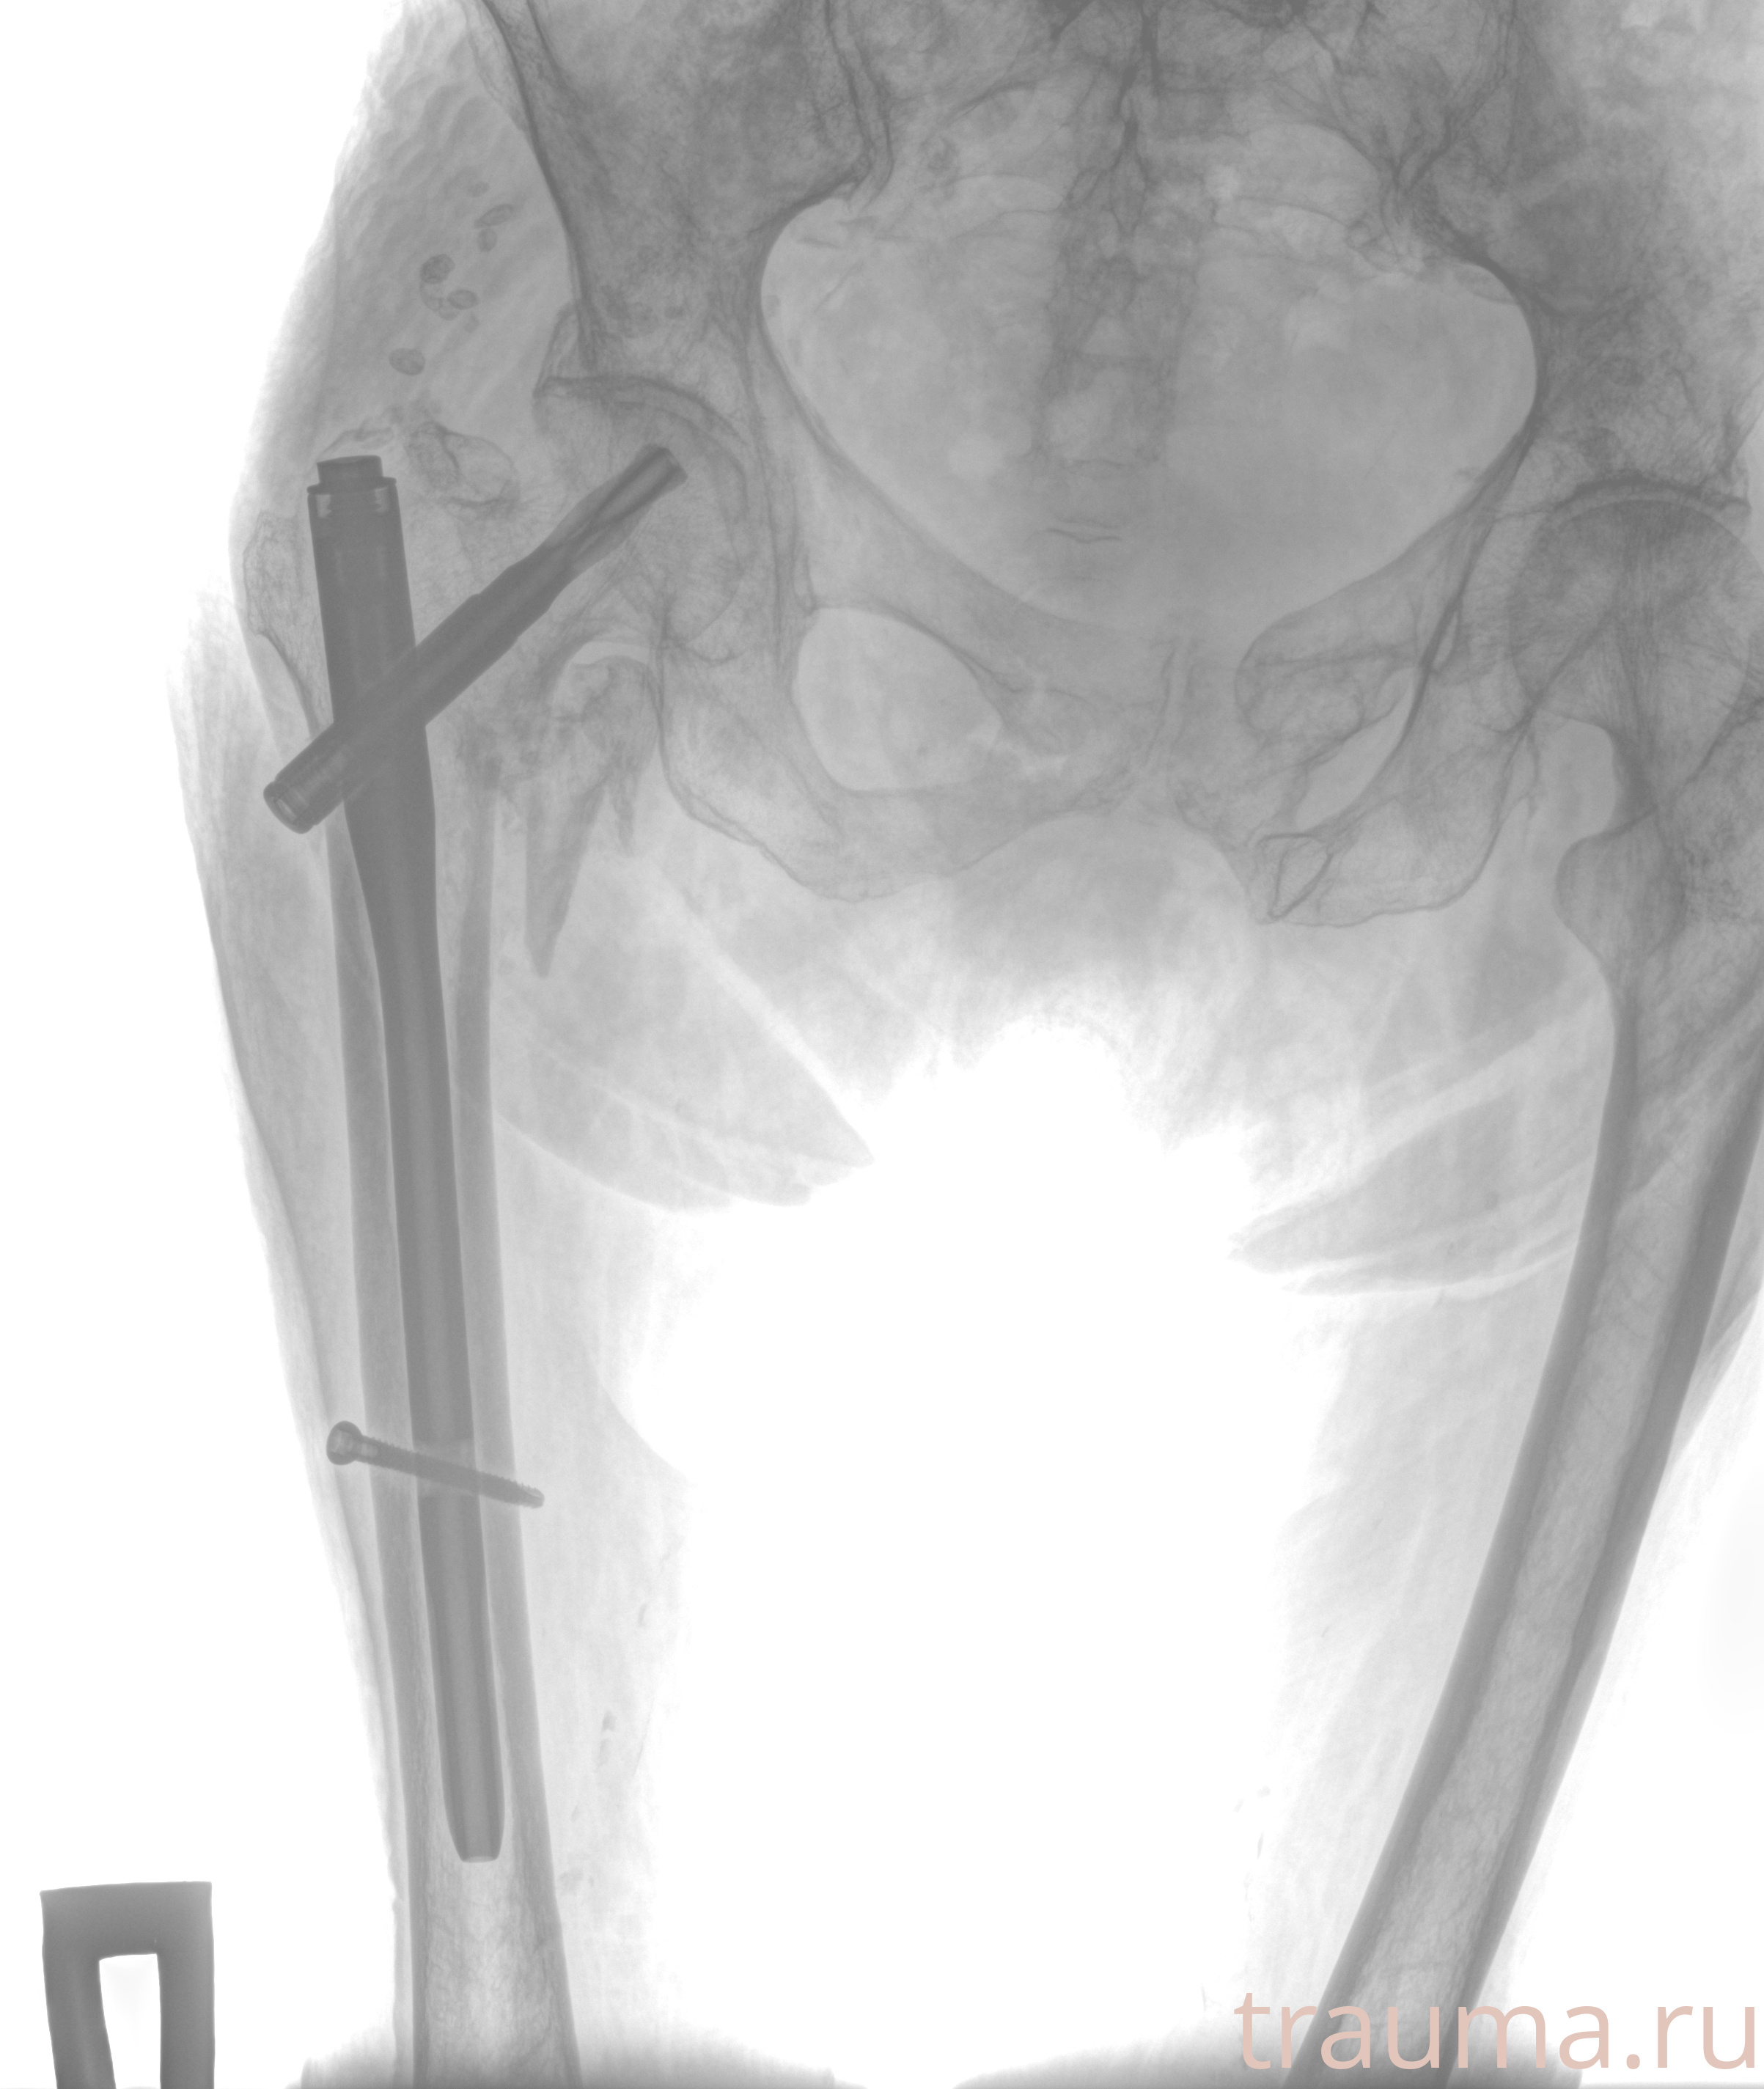

Рентгенограммы

Рентген на дому: по вашему адресу приезжает врач-рентгенолог, травматолог-ортопед с мобильным рентгеновским аппаратом, проводит диагностику травмы или заболевания, делает необходимые рентгенограммы, дает рекомендации по дальнейшему лечению. Получить качественные снимки в домашних условиях возможно благодаря уникальной методике, разработанной МосРентген Центром для института  Склифосовского